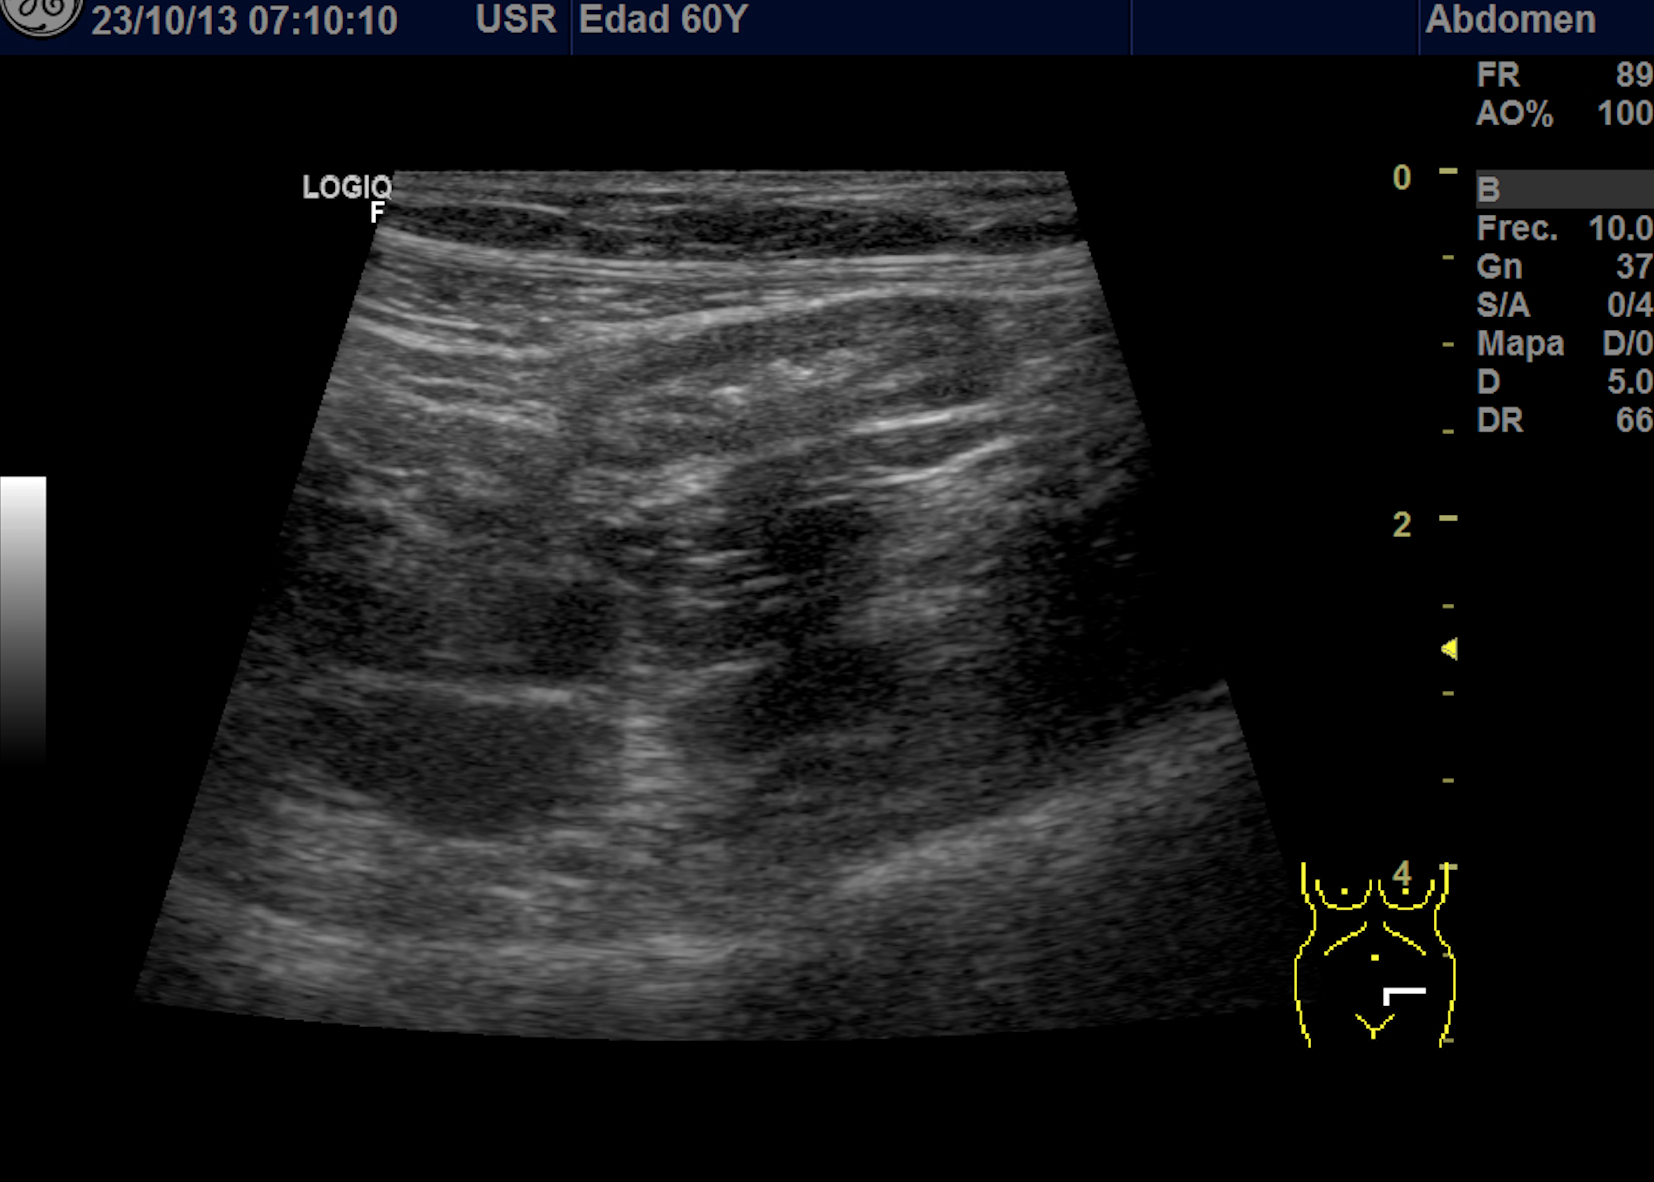

Hallazgos ecográficos

Se explora FII-hipogastrio y en el punto de más dolor se observa engrosamiento de asas de intestino grueso sin peristaltismo y con signos de edema de la grasa adyacente. No líquido libre.

También se realiza ecografia en urgencias del hospital.

En el hospital se realiza una nueva ecografía en el servicio de radiología confirmando el diagnóstico de sospecha: diverticulitis aguda en sigma distal sin datos de complicación. Hinchey 1A.